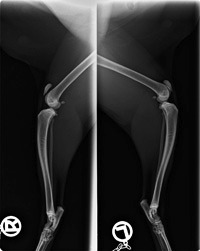

„Ragnar“, ein Kitten aus dem Pointwurf ist bei und geblieben. Er selbst ist kein Colourpoint, doch er ist ein Pointträger. Als solcher bei TICACATS registriert und nicht zur Zucht zugelassen. „Ragnar“ zeigt deutliche Deformationen und extreme Fehlstellungen an den Vorderbeinen und den Hinterbeinen vom Becken abwärts. Sowie einen gestörten Skelettaufbau (seine Körperproportionen zu einander stimmen nicht) einen Knickschwanz und eine unterschiedliche Dichte der Knochensubstanz. Was aufgrund von Röntgenbildern ersichtlich ist.

Da konnte der Kleine ganz plötzlich nicht mehr laufen, er hatte große Schmerzen und sich nicht mehr getraut die Hinterbeinchen zu belasten. Er konnte nur noch liegen. Es wurde eine schwere beidseitige PL diagnostiziert und eine schnelle Operation war unumgänglich. Wir bekamen einen schnellen Termin in der Tierklinik und die OP verlief erfolgreich. Im Zuge der OP hat man bei „Ragnar“ eine HD (durch unvollständig ausgebildete Gelenkpfannen), mit einer beginnenden Arthrose festgestellt. In der Tierklinik staunte man nicht schlecht über seine krummen Beinchen und seinen seltsamen Wuchs. Solche krummen Knochen in diesem Ausmaß kannte man dort von Katzen bisher noch nicht. Ähnliche Missbildungen waren nur bei Hunden (Dackeln) bekannt.